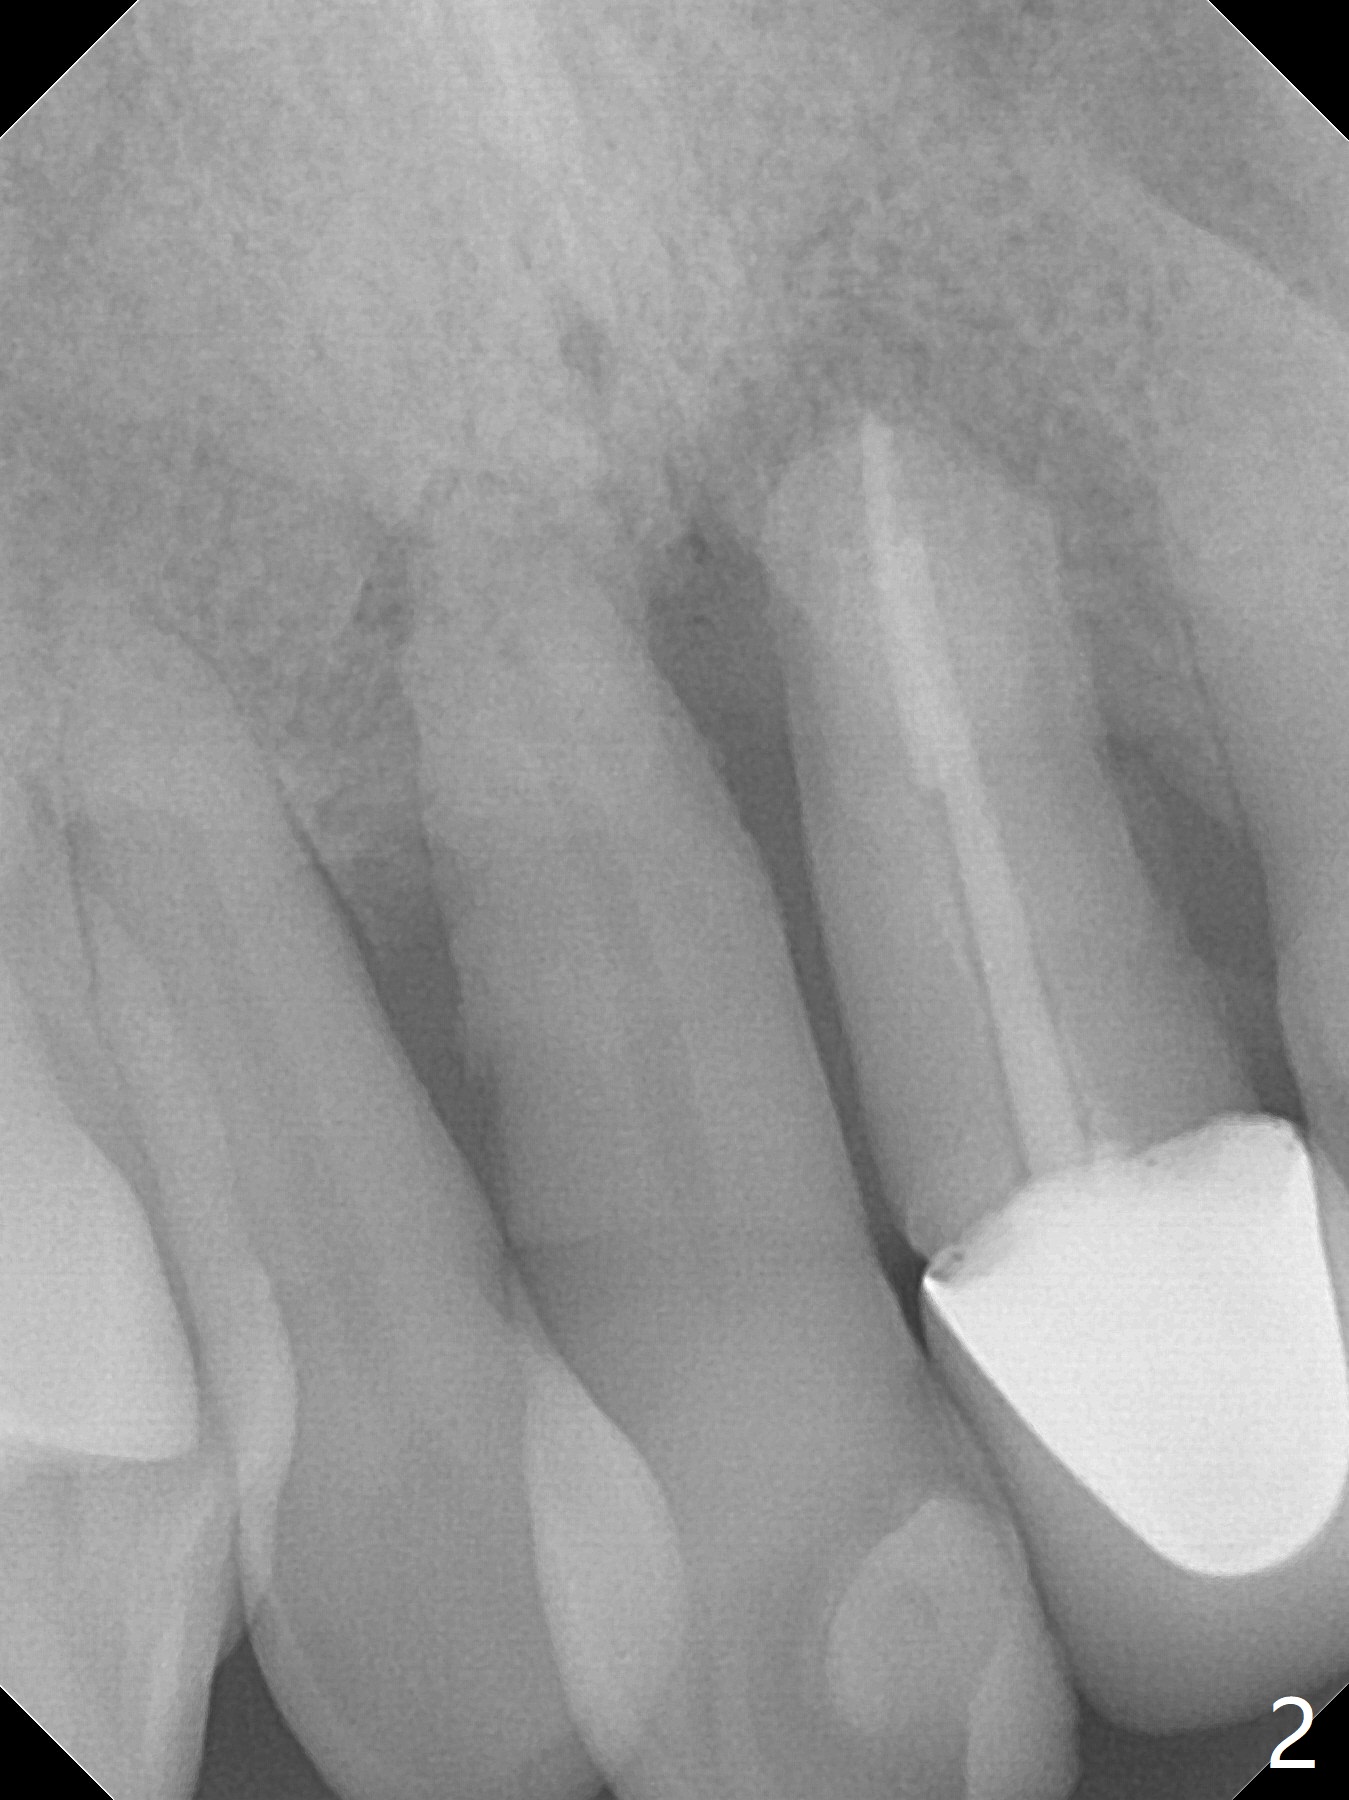

A 59-year-old man requests treatment for buccally displaced upper central incisors (Fig.1,2). It appears that the buccal plate is lost, but the bone height will allow placement of 3.5x13 mm implants with guide (Fig.3). Because of severe infection apical to the tooth #8 (Fig.4,5 *) and truncation of the incisal edges of the upper central incisors during CBCT taking (Fig.6,7 *), guided surgery may not be appropriate. The mesial surfaces of the teeth #7 and 10 and the incisal edges of the lower incisors (*) will be trimmed for immediate provisional. Immediate implants will be placed in the palatal crest of #8 (Fig.6 <) and close to the palatal crest of #9 (Fig.7). Angled abutments are expected (4.5x15 degree, A or B (4 mm cuff). PRF is to be preparedx2 (one for membrane; the other for sticky bone). Take Alginate impression when the patient returns for surgical stent.